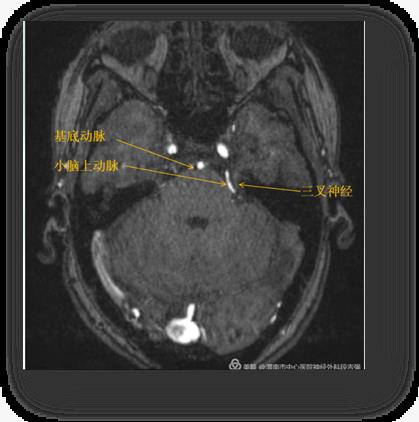

6月23日,市中心医院神经外科一病区段吉强主治医师在门诊接诊了一名中年女性,该患者左眼睑及眉弓上部持续疼痛数日(中间有短暂缓解期),异常痛苦。追问病史得知,患者已被病痛折磨了2年,口服药物“卡马西平片”逐渐对其失去控制,近几日口服止痛药物也收效甚微。门诊初步诊断“左侧三叉神经痛”。经过术前磁共振检查确定了左侧小脑上动脉压迫左侧三叉神经出脑干区。

关于原发性三叉神经痛的发病机制,目前较为流行的假说是血管压迫三叉神经节,最终导致神经纤维脱髓鞘改变,提示解除三叉神经压迫可能治愈三叉神经痛。